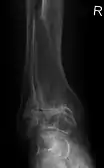

هشاشة العظام الشديدة وهشاشة العظام في المفصل الرسغي

هشاشة العظام الابتدائية في الركبة اليسرى. يلاحظ وجود عظيمات، وضييق المساحة داخل المفصل (السهم)، وزيادة كثافة العظام تحت الغضروف (السهم).